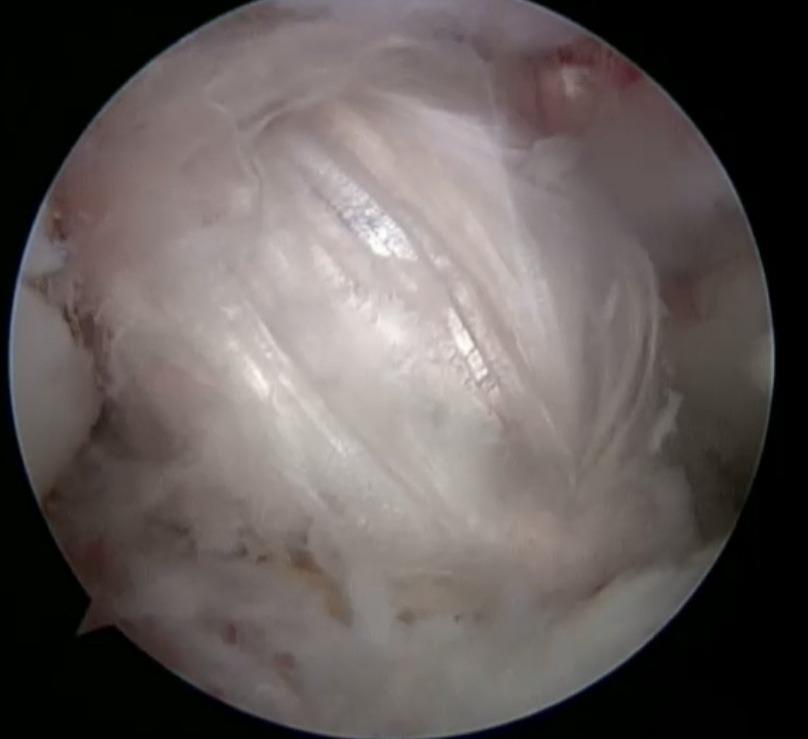

Наложения артроскопического шва заднего рога медиального мениска

Субтотальный разрыв передней крестообразной связки, частичное повреждение медиальной коллатеральной связки и структур латерального коллатерального комплекса, околокапсулярный разрыв заднего рога медиального мениска.

По итогам исследования и определения диагноза пациенту был предложен и реализован план лечения: предоперационная реабилитация и проведение операции по поводу наложения артроскопического шва заднего рога медиального мениска, а также проведена пластика передней крестообразной связки сухожилием полусухожильной и тонкой мышц правого коленного сустава.